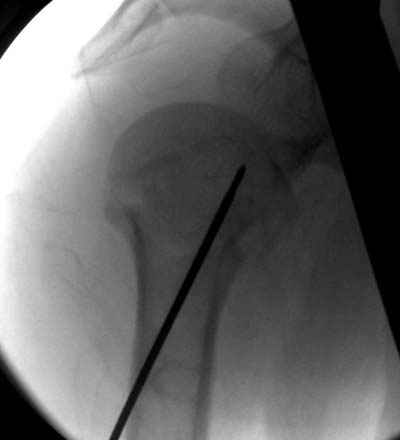

Женя, а как ты водишь спицы, в смысле, как делаешь входное отверстие, и как в него проводишь V-спицу? А то о дна из спиц, та, у которой не дошла до головки одна палочка буквы V, как-то выглядит на рентгенограмме, как будто или через очень большое отверстие введена, или каждая половинка через отдельные отверстия.

Мне кажется, проблема в том, что не все концы спиц зашли в головку, и зашедшие - недостаточно далеко прошли.

Спицы провожу по передней и задней поверхностям плечевой кости через 4,5 мм отверстия на разных уровнях.

V-спица проводится через 4,5 мм отверстие. Видимо, из-за разной длины вторая половина спицы *пролетела* мимо отверстия, что и привело к вторичному смещению костных фрагментов.